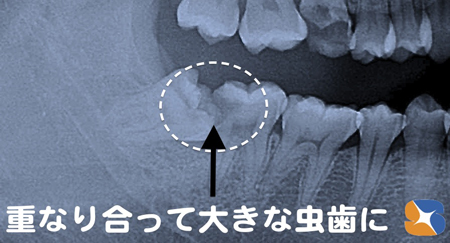

Dr:「横向きに生えている親知らずと隣り合わせの歯が重なり合い、そこに食べ物が挟まり続けて虫歯になったようです。

親知らずは、抜歯します。その隣りの歯は抜かずに残せますが、神経だけは抜く必要があります。点滴をしながら、一度に両方の治療を行いますので、がんばっていきましょう!

〈レントゲン画像〉横向きに生えている親知らずの歯と重なりあっている所に食べ物が挟まり、きつい痛みを伴う大きな虫歯になりました。